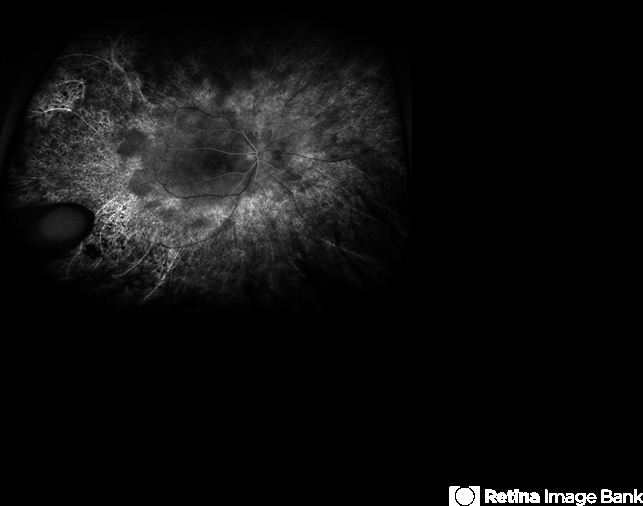

- retinitis pigmentosa (RP) dystrophy

- 20-year-old patient with retinitis pigmentosa and pars planitis, recently s/p Retisert implant